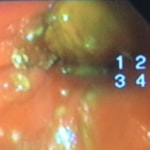

経過:超音波検査にて直腸壁の肥厚(5㎜)が認められた。また、直腸検査で直腸全周に結節状病変を触知し、出血も確認された。消炎剤、抗生剤、整腸剤による治療への反応が長期的に悪いため、生検も含めた内視鏡検査を実施した。

内視鏡検査:肛門付近の直腸全周に、炎症および出血を伴う結節状病変を多数認めた。

病理検査:直腸の病変は、良性の非腫瘍性病変の一つである“炎症性ポリープ”と診断された。